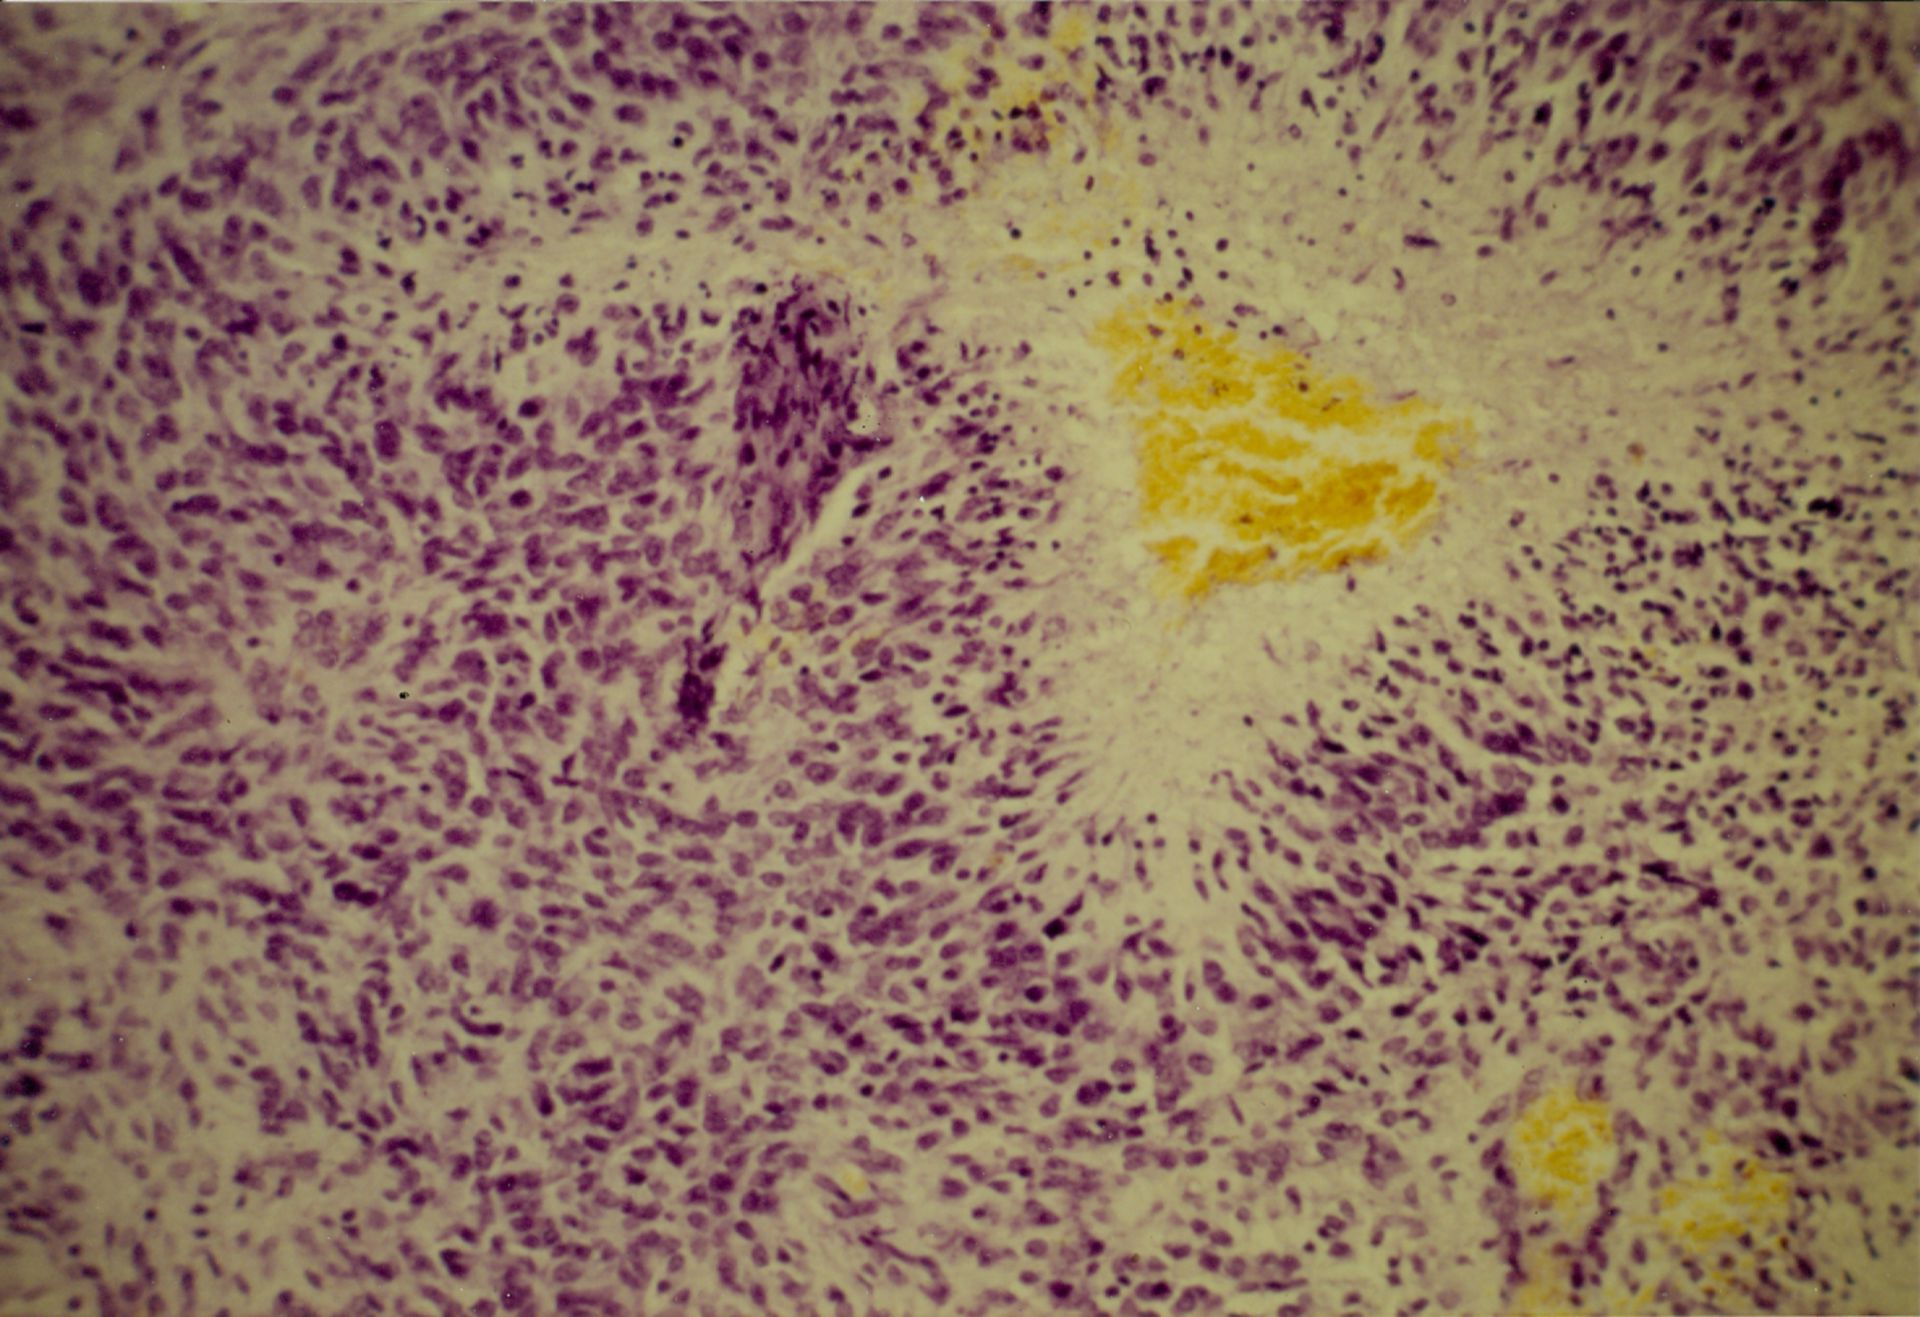

Микрофотографии гистологии глиобластомы головного мозга